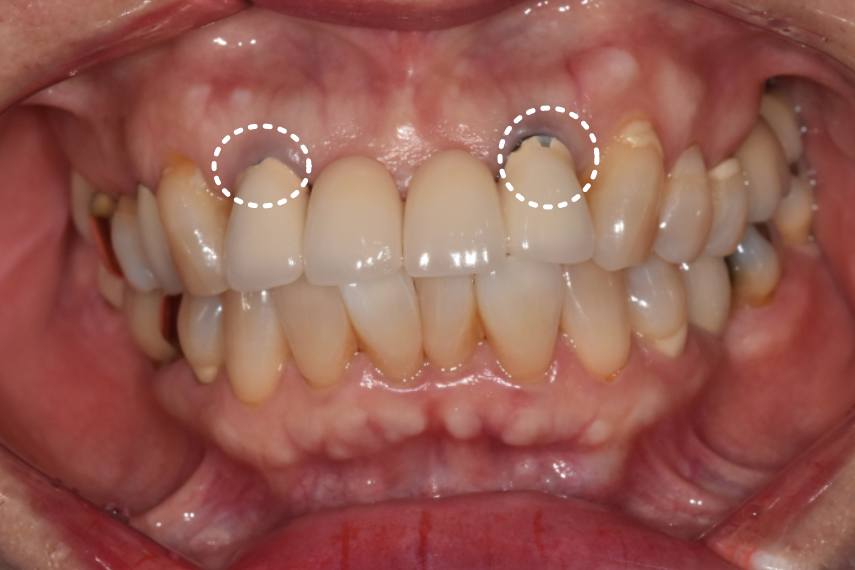

기존 브릿지를 살펴보니 도자기 재질이었는데

군데군데 깨져 있습니다.

240622

또 양쪽 끝 치아 2개에 포스트(기둥)가 박혀 있었습니다.

포스트를 했다는 것은 치아머리 부분이 많이 없었다는 뜻입니다.

즉, 치아가 약한 상태였던 거죠.